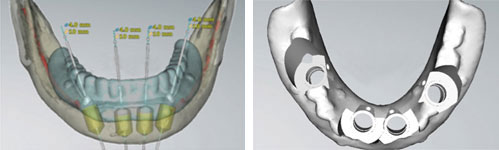

1 通过高智能数字化检查系统扫描得到口腔精准数据,同时兼顾后期修复等诸多因素进行综合考虑,量“齿”定制一种顶级高难度治疗方案——穿颧种植,帮助张阿姨恢复一口好牙! 01 什么是穿颧种植? ![]() 穿颧种植:穿颧种植被称为是当今难度较高的种植技术,指的是颧骨固定种植技术,该技术无论稳定性还是受力性都非常好,也是当今难度较高的种植技术。适用于上颌骨切除、上颌骨重度萎缩、常规内外提升都没有办法达到种植条件的无牙颌患者,通俗地被人称为“无土培栽技术”。 02 为什么说“穿颧种植” 是种植界的“珠穆朗玛峰”? 穿颧手术的关键还是在于患者剩余骨量比较少,需要做一个比较长的颧种植体,植入颧骨区。因为患者牙槽骨严重萎缩,暴露口腔颌骨区域比较少,需要医生对解剖结构比较了解,才能在有限的视野里面成功植入一个比较长的颧种植体。因此,对医生术前设计和术中的操作以及临床经验是一个比较大的考验。 03 穿颧种植和常规种植相比效果如何? 穿颧种植由来已久,国外已经开展多年。综合来看穿颧种植与常规半口全口种植远期的成功率是没有根本区别的,可能只是选择的骨头位置不太一样。在国际上来看,穿颧种植10年里面的成功率大概在97%左右。 1、感觉更舒适,更自然,坚固耐用 2、具有很好的固位效果 3、使咀嚼效率达到与自然牙媲美的程度 4、刺激骨组织,延缓颌骨的吸收与萎缩 5、不损伤邻牙,并且能有效地保护邻牙 ![]() 数字化种植牙技术是将计算机断层扫描技术(CT)、计算机辅助设计技术(CAD)和快速原型制造技术(RP)综合应用于种植手术的放心、准确的方法。 |